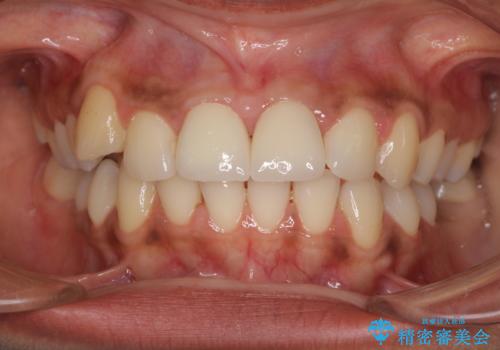

- 上の前歯2本の審美障害を気にして来院された患者様です。樹脂が無造作に充填されており、色合いも形態も不自然で、歯肉も腫れているため、オールセラミッククラウンにて補綴することとしました。

充填されたレジンを取り除いたところ、歯肉の炎症による出血が認められました。セラミッククラウン装着後は歯肉が腫れることもなく、仕上がりも自然な歯のようになり、患者様には大変満足していただきました。